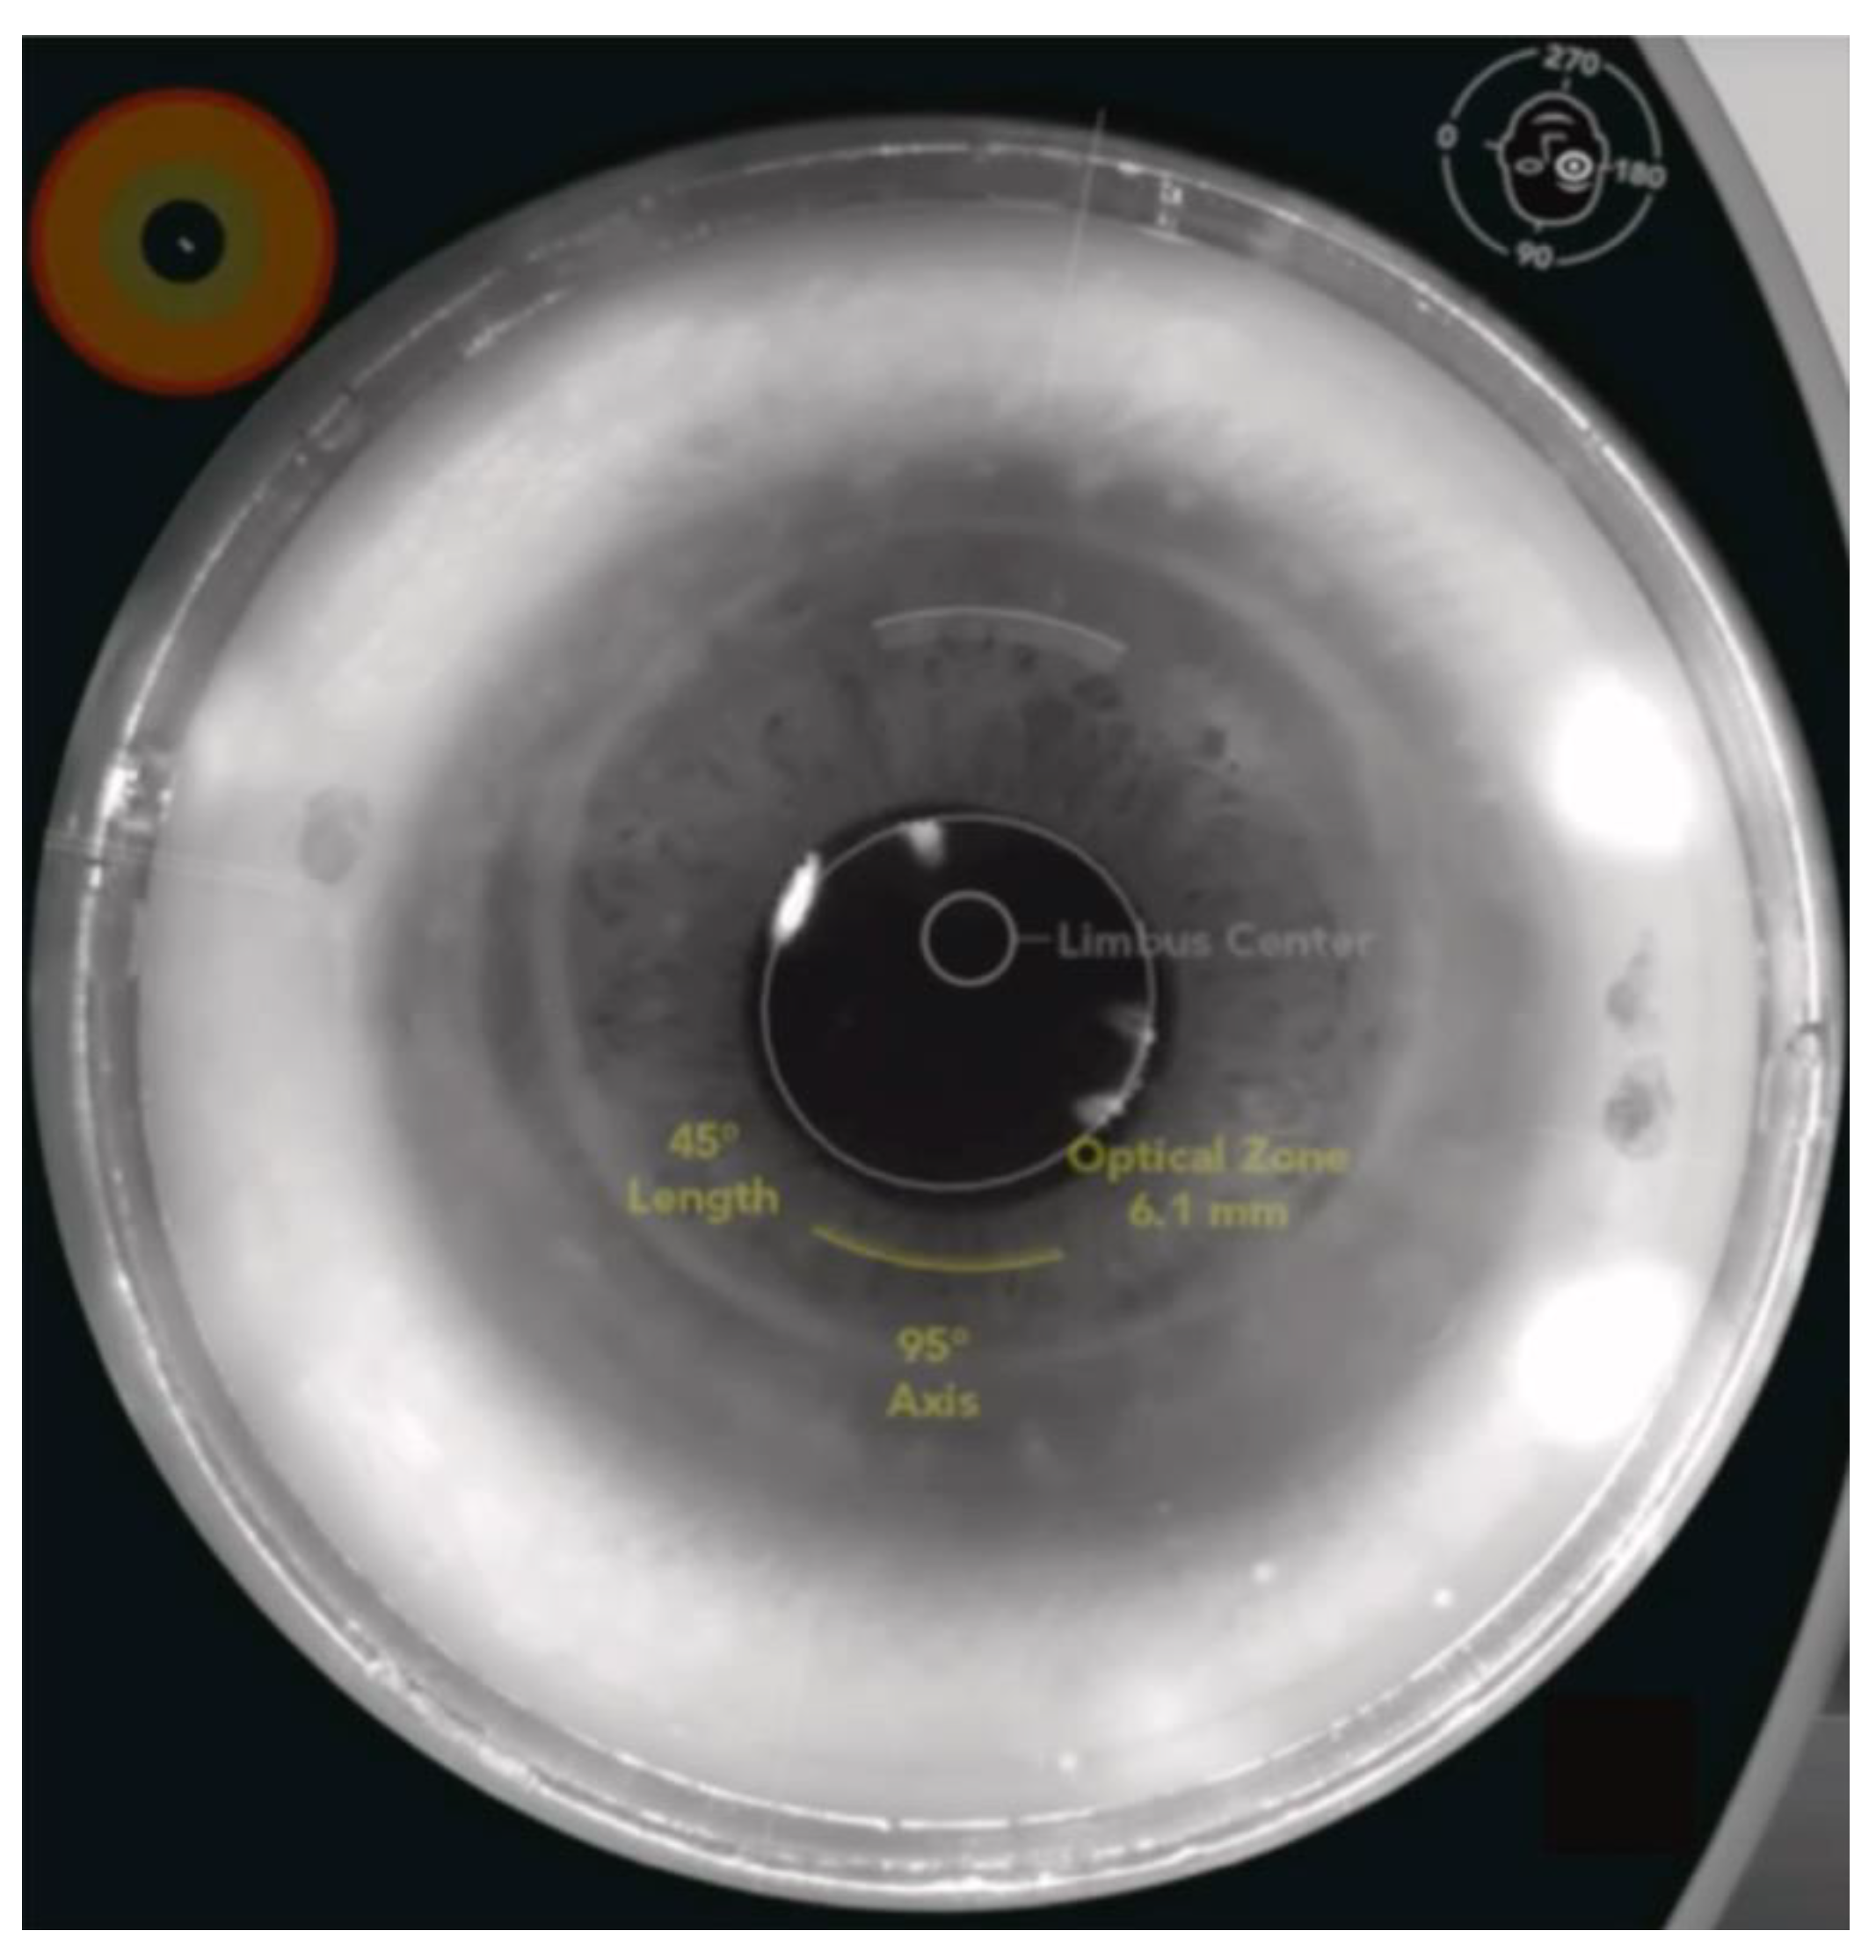

Figure 5.

An example of FS-AK using the Catalys FSL platform in an eye after penetrating keratotomy. FS-AK is located on the donor side of the cornea and can be customized in length, depth, location, and treatment axis [6].